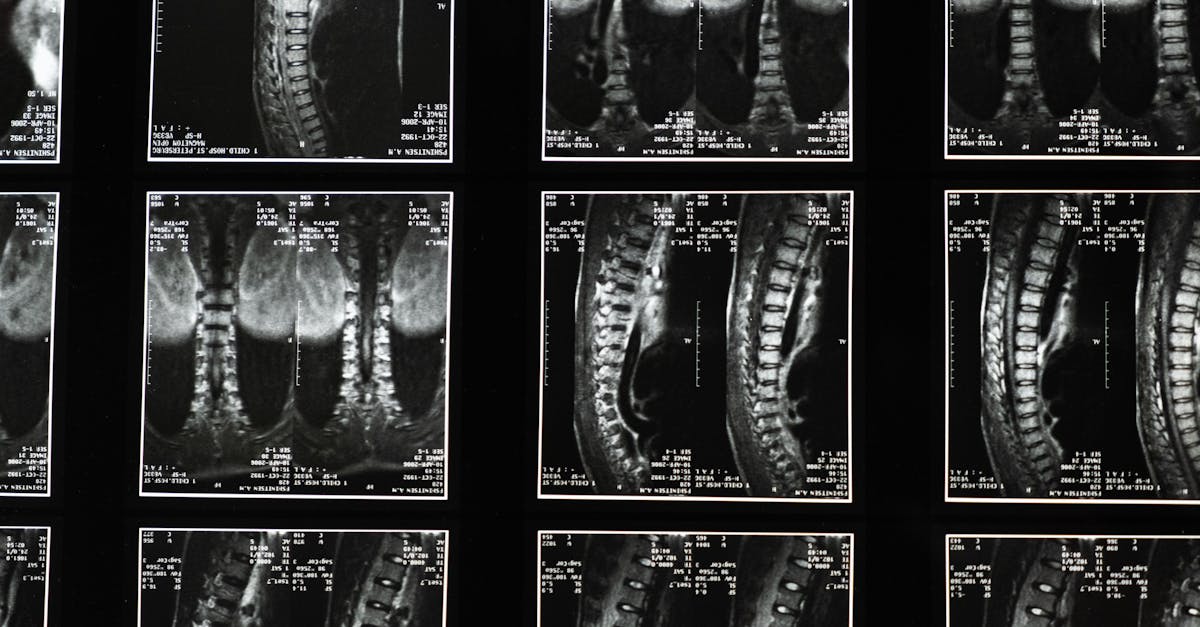

If pain persists or worsens despite self-care, professional evaluation is important. Physical therapists and chiropractors can tailor treatments which may include manual therapy and guided exercises. In some cases, imaging studies are necessary to rule out serious conditions.